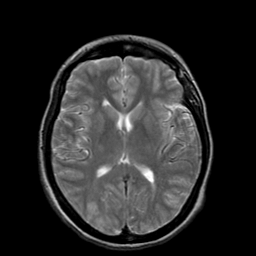

Hypertensive Encephalopathy, overlay -- Slice #13

[Home][Help][Clinical] Slice 13